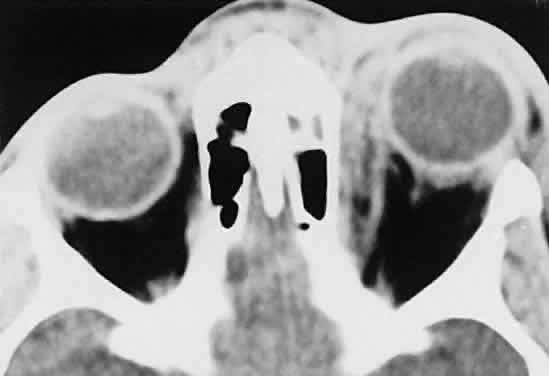

Within the orbit, rhabdomyosarcoma occurs most often, but not exclusively, in the superior nasal quadrant, with downward and outward displacement of the globe. CT scans show the topography of the orbital mass (Fig. 1A), as well as the possible extension into adjacent bone, paranasal sinuses, or the intracranial cavity. The circumscription that may be noted on CT is relative, because the lesion is not encapsulated and microscopically infiltrates normal tissue. Echography shows internal echoes of low-to-medium amplitude. Because the cellular tumor absorbs acoustic energy, the amplitude of the spikes falls off somewhat through the lesion (see Fig. 1B and C). MRI can help define the tumor's relationship to extraocular muscles (Fig. 2).

Fig. 1. A. Proptosis and downward, outward globe displacement developed over 2 days in a 3-year-old girl. A homogeneous mass fills the superomedial orbit. B. Contact B-scanning shows a relatively well-circumscribed mass with uniform internal echoes. C. Contact A-scanning shows the internal reflectivity to be of low to medium amplitude, consistent with a sarcomatous lesion. Biopsy results confirmed the diagnosis of rhabdomyosarcoma.